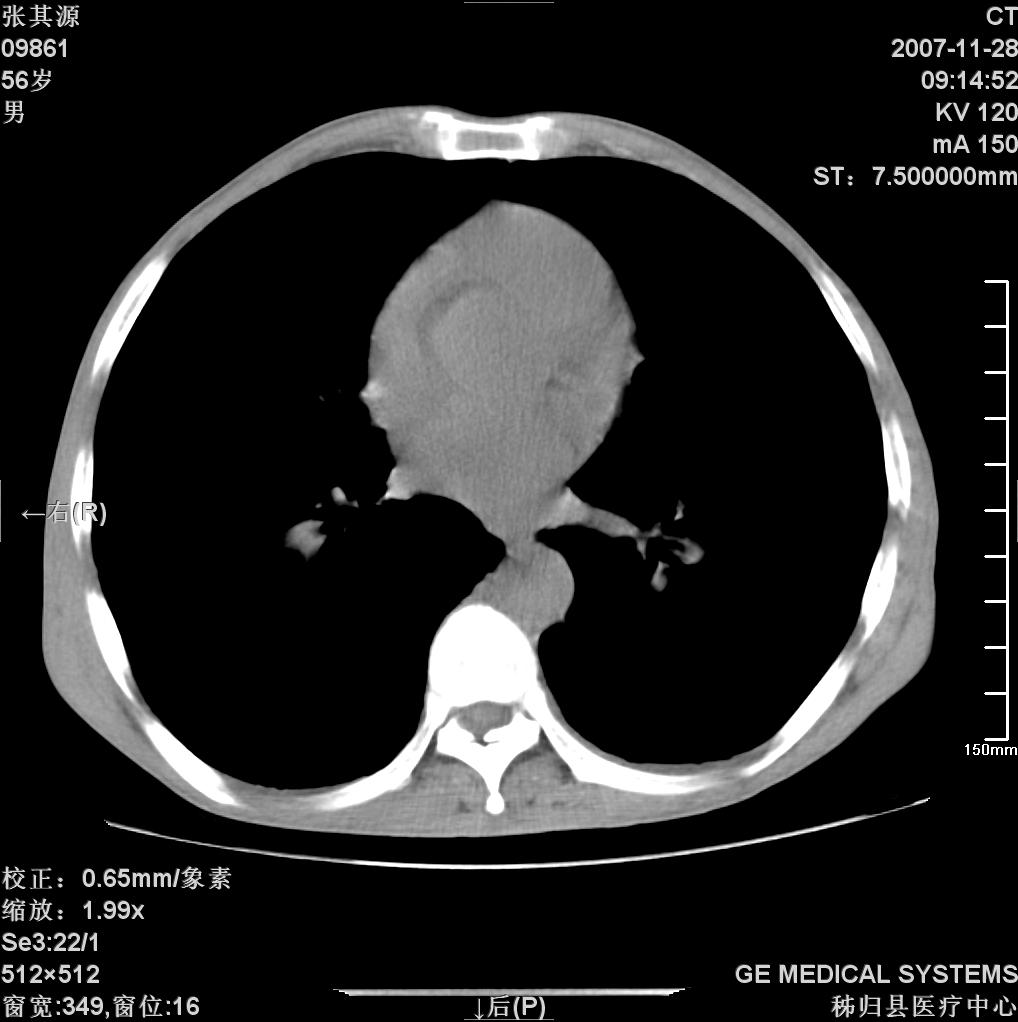

患者因阻塞性黄疸入院,发病前10天持续中等程度发烧.术前检查发现两肺弥漫性病变,请各位大虾会诊,除了考虑急性血源性肺结核外,还有其他什么疾病可能.

考虑tb不排除转移,(隆突处有肿大淋巴结,不好说是结核还是转移引起的)

双肺多发粟粒样病灶,右肺胸膜下结节样病灶,气管前腔静脉后及隆突下均见肿大淋巴结,结合胆道肿瘤病史首先考虑转移。另外心影密度略低,时间格显示,是否有贫血?查明白再手术吧!